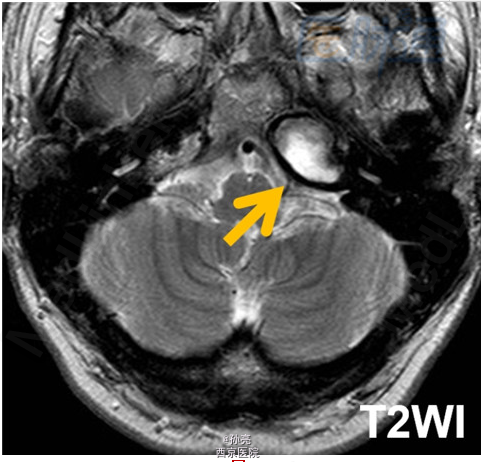

50岁男性,长期左侧耳聋。

CT检查多表现为颞骨岩尖部出现边界清楚的囊性膨胀性病变(图A箭头)。由于包块内血液分解产物和蛋白质碎片的积累,其在MRI检查时,多表现为T1和T2加权图像上的高信号影(图B箭头)。在MRI的T2加权图像上,可见到包块的周围有明显的低信号影包绕。而这主要是由含铁血黄素在局部的沉积所致(图C箭头)。此外,包块多无扩散受限(图D箭头)。